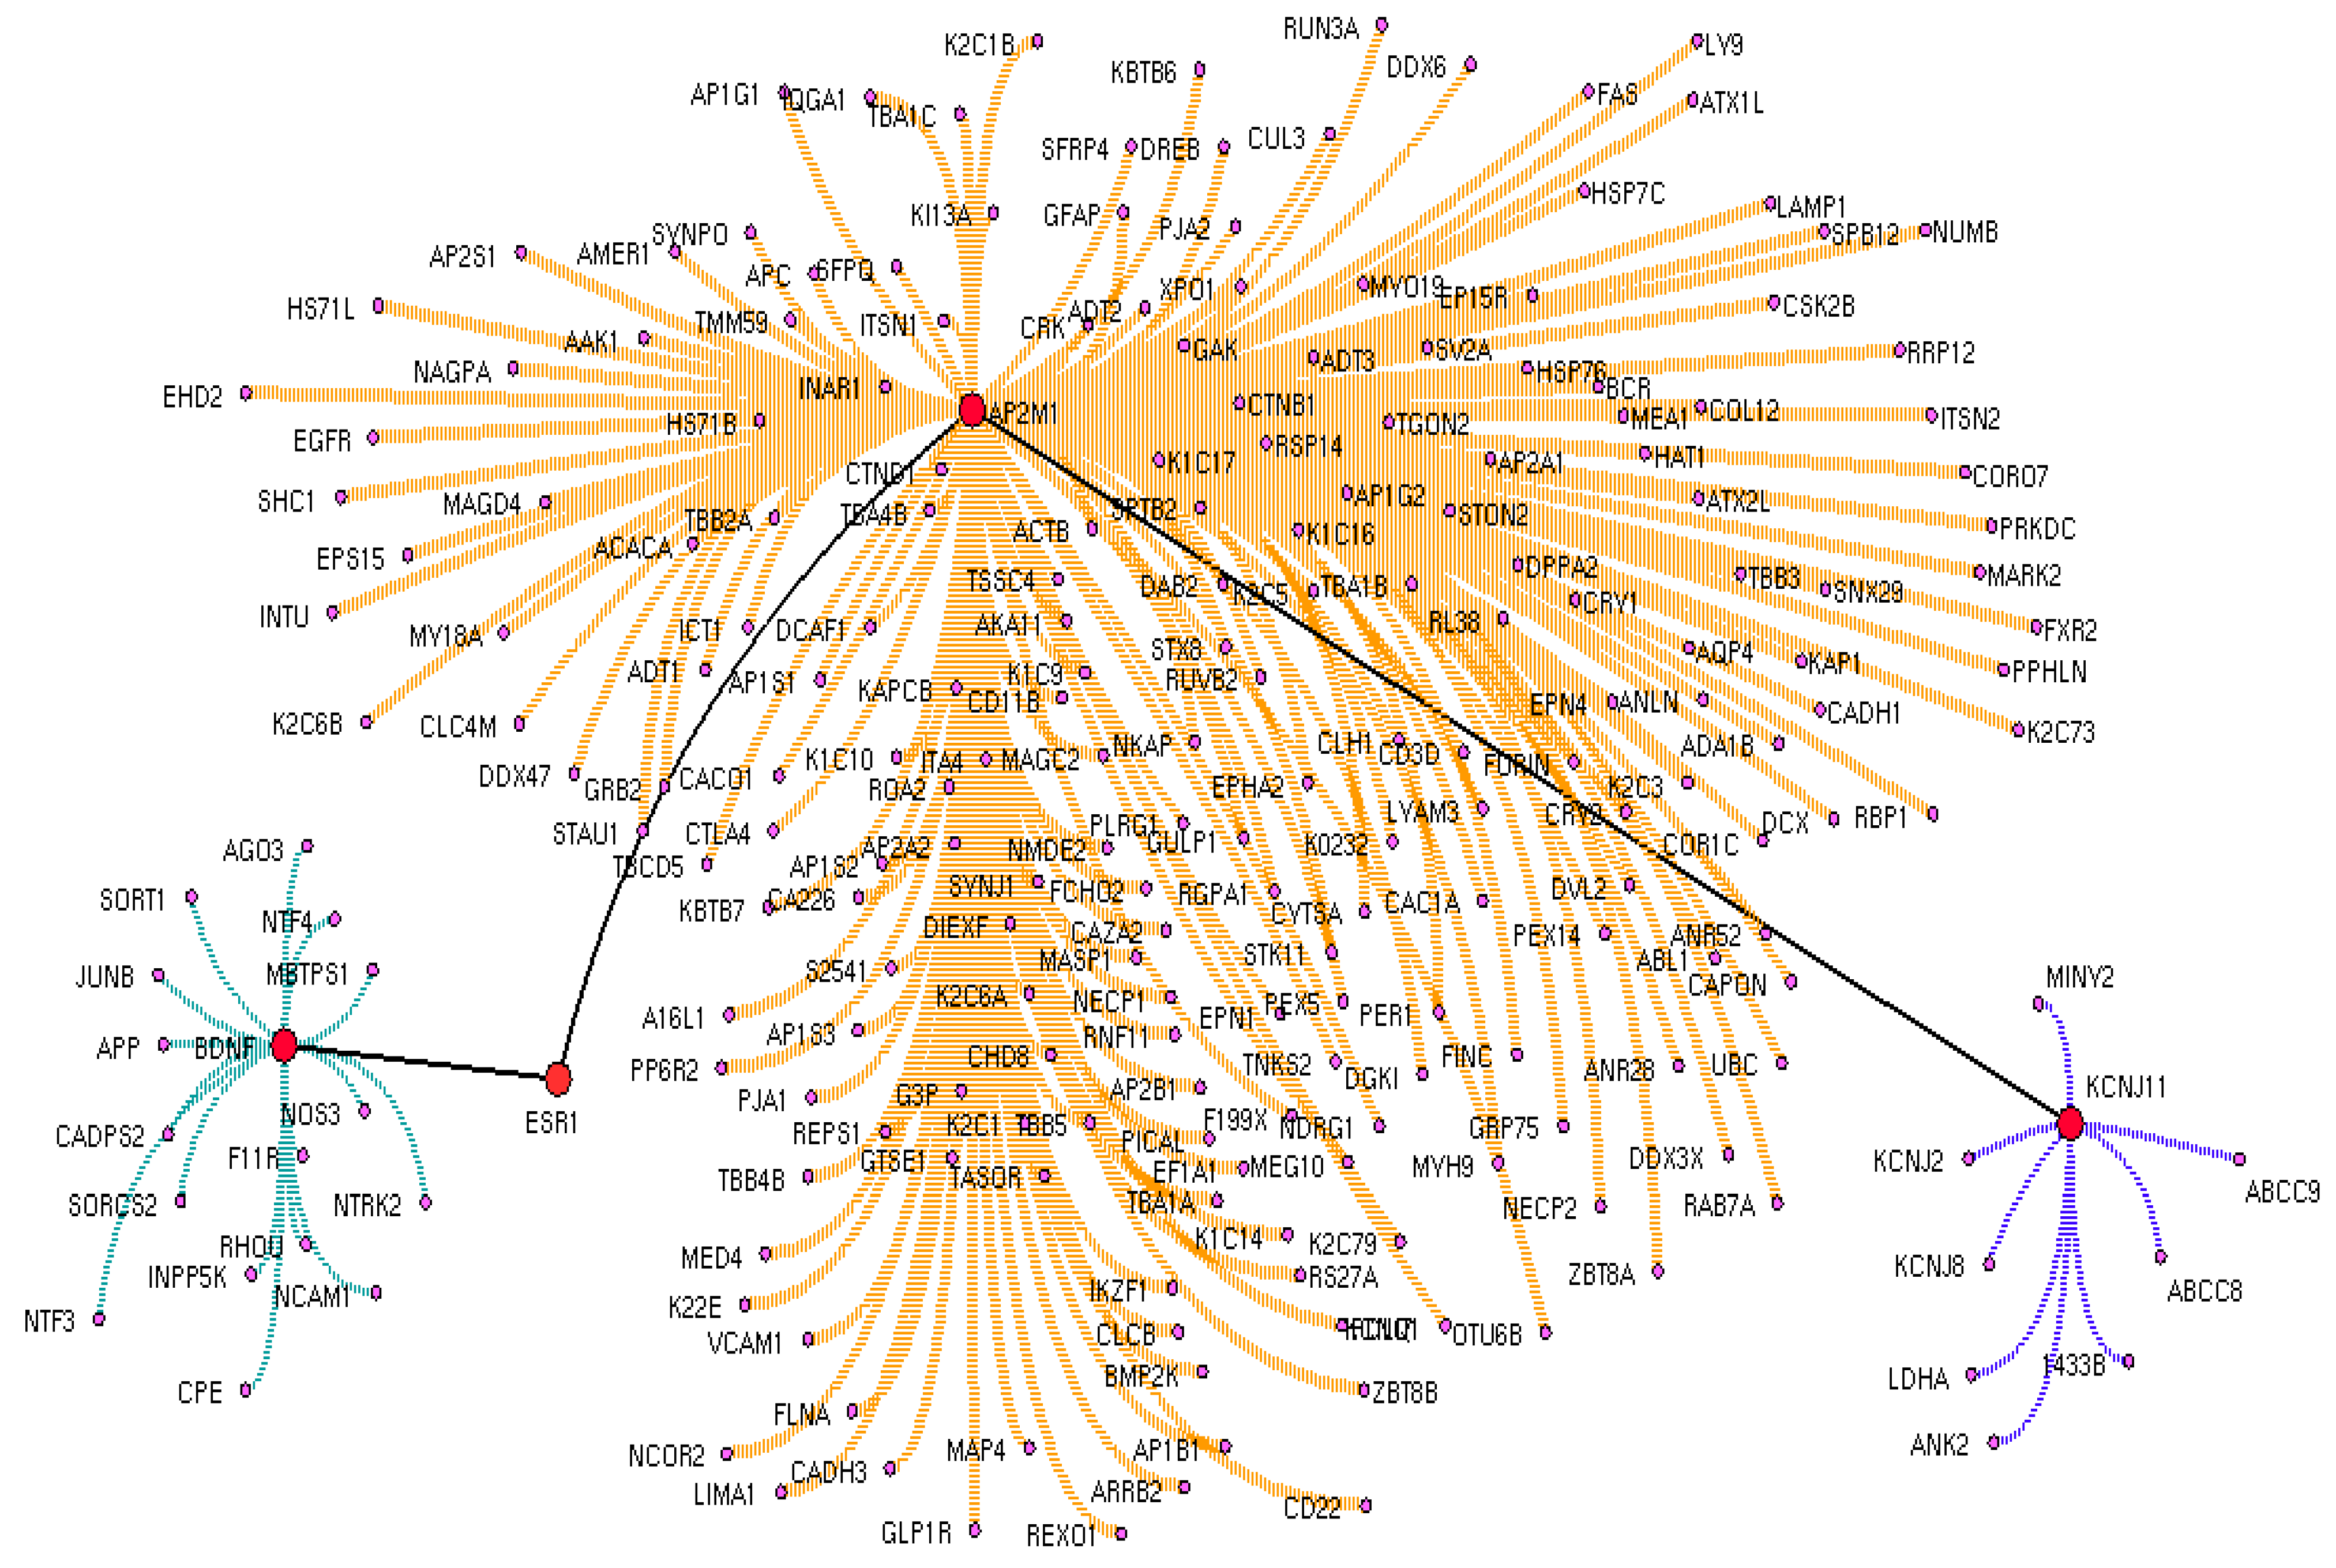

3.2. Drug Interactome Enrichment Analysis

3.3. Crucial Protein in Drug Interactome